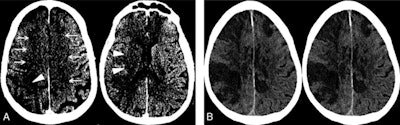

The current case study from Allegheny Health Network Stroke Center in Pittsburgh is of a 64-year-old man who presented to the emergency department after waking up at home with symptoms of left-sided paralysis and shortness of breath. He had tested positive for COVID-19 16 days prior and was recovering well before his sudden onset of ischemic stroke. The patient passed away from complications of COVID-19 three days after admission to the hospital.

Image A: Noncontrast CT on the day of admission demonstrates subtle findings of acute ischemia in the right middle cerebral artery (arrowheads) and bilateral anterior cerebral artery (arrows) territories, including hypoattenuation and loss of gray-white differentiation. Image B: Repeat noncontrast CT on hospital day two demonstrates progression of acute infarcts in the right middle cerebral artery and bilateral anterior cerebral artery territories, including worsening edema and mass effect. Image courtesy of AJNR.Data about COVID-19 gathered around the world suggests 5% to 6% of patients with severe cases may suffer a cerebrovascular injury.